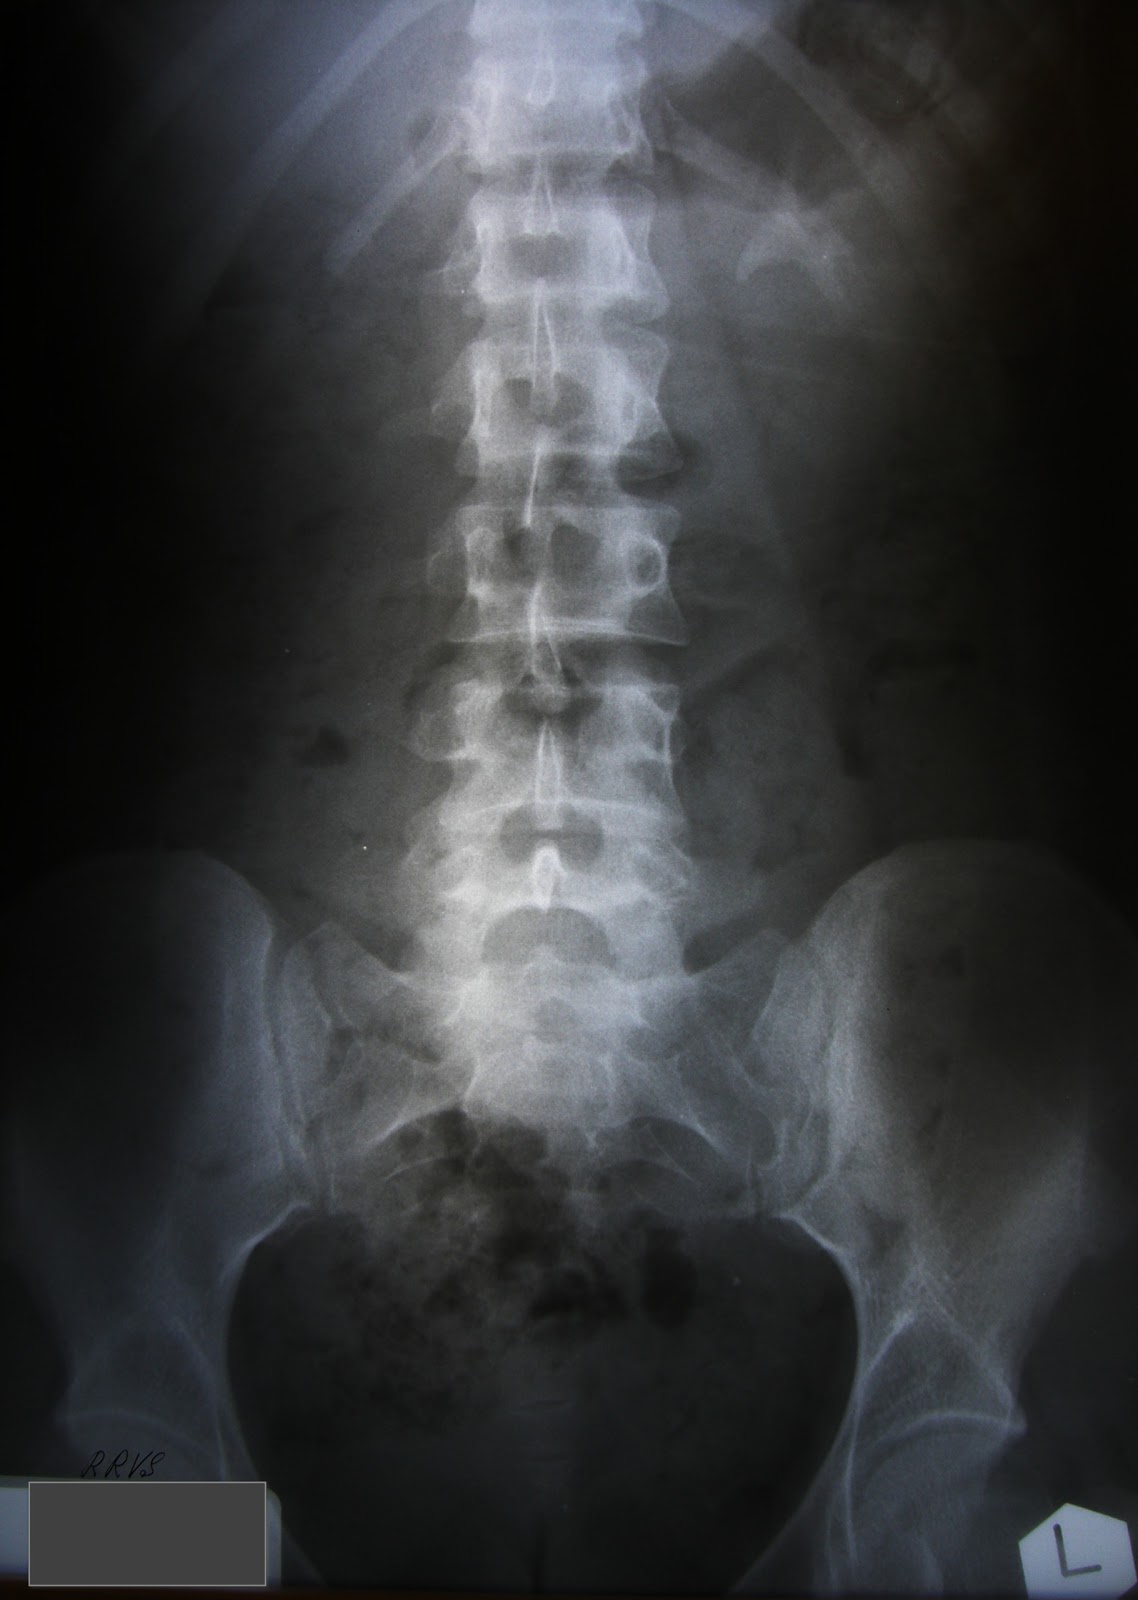

Эффективные методы удаления коралловидного камня из почки: проверенные советы

Узнайте, как безопасно и эффективно избавиться от коралловидного камня в почке с помощью наших рекомендаций и советов.